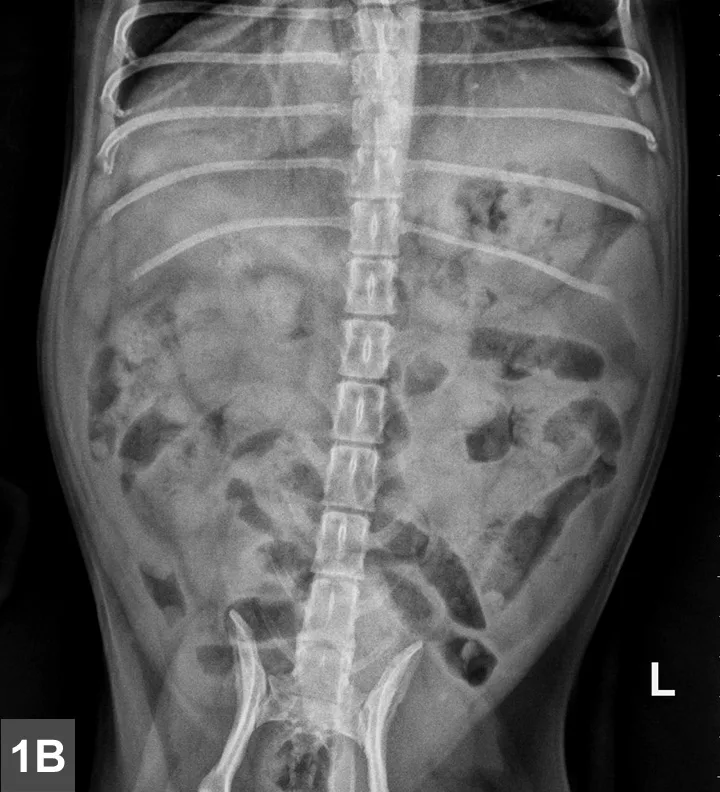

Left lateral (Figure 1A) and VD (Figure 1B) radiographs of the abdomen were obtained. Although thoracic radiographs were also taken, the findings were considered normal and, therefore, are not included here.

Figure 1A & B

Left lateral (Figure 1A) and VD (Figure 1B) views of the abdomen.